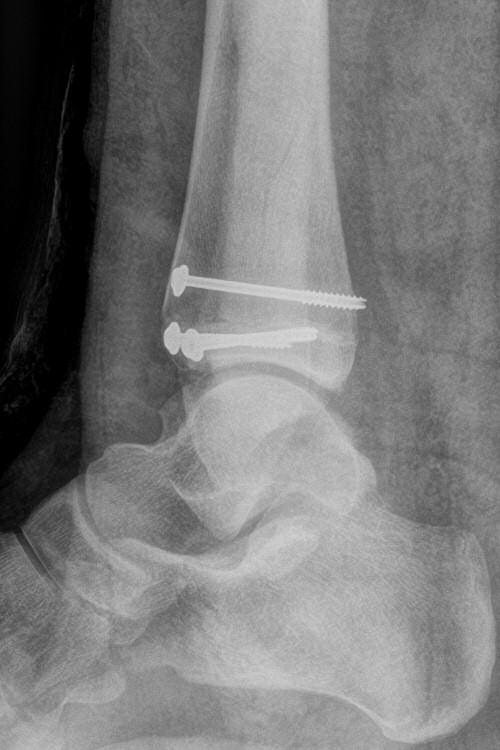

Distal tibiafyseolys SH 4 triplansfraktur (barn)

Triplanfraktur = triplansfraktur = treplansfraktur: fraktur i distala tibia som engagerar både metafys, fys och epifys. Kan vara 2, 3 eller 4 fragment. I 50 % av fallen är även fibula frakturerad [3].

Exempel på triplansfraktur hos nästan färdigvuxet barn

Efter operation med skruvfixation

- Förbered för inläggning och snar operation, ofta med kanylerade skruvar. [2]